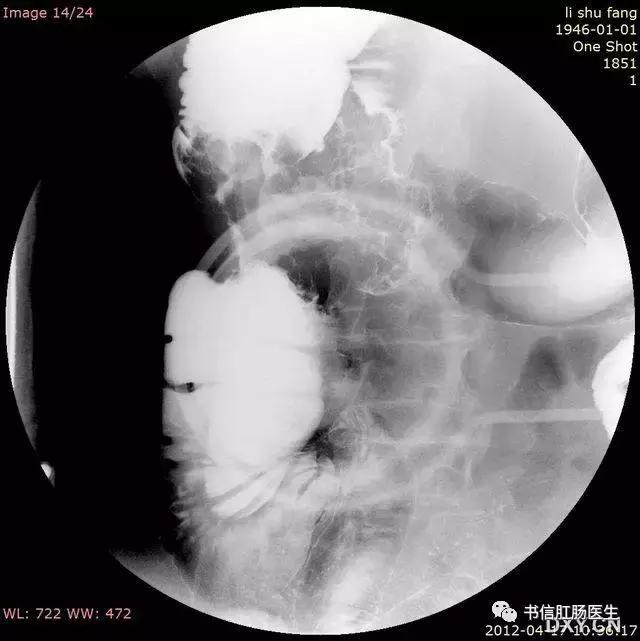

★ 一例绞窄性性肠梗阻形似「咖啡豆」

■ 影像表现:仰卧位腹部平片上表现为肠管透亮区形成类似咖啡豆样的形态。

■ 征象解析:肠管部分性嵌闭时,扩张的闭襻内因充气而透明,正中为折叠后相靠近的两端肠内壁形成的条状致密带,形如咖啡豆,称咖啡豆征。咖啡豆征是乙状结肠扭转的经典 X 线表现,是因为乙状结肠闭襻积气扩张,肠管的内侧壁并列形成咖啡豆征的裂隙,而扩张肠管的侧壁形成咖啡豆征的外侧壁。

■ 讨论:咖啡豆征可以用来描述小肠闭襻型梗阻,但更多用于描述乙状结肠的闭襻型梗阻。假如仰卧位腹部平片不能明确诊断时,行单纯的钡剂灌肠检查,在扭转的部位会出现钡柱突然中断,而呈鸟嘴样或鸟嘴征。但钡剂强制性通过扭转部位可能会导致穿孔或使不完全梗阻转变成完全梗阻。当患者出现肠缺血或肠穿孔时,不能行钡剂灌肠检查,而应立即行手术治疗。